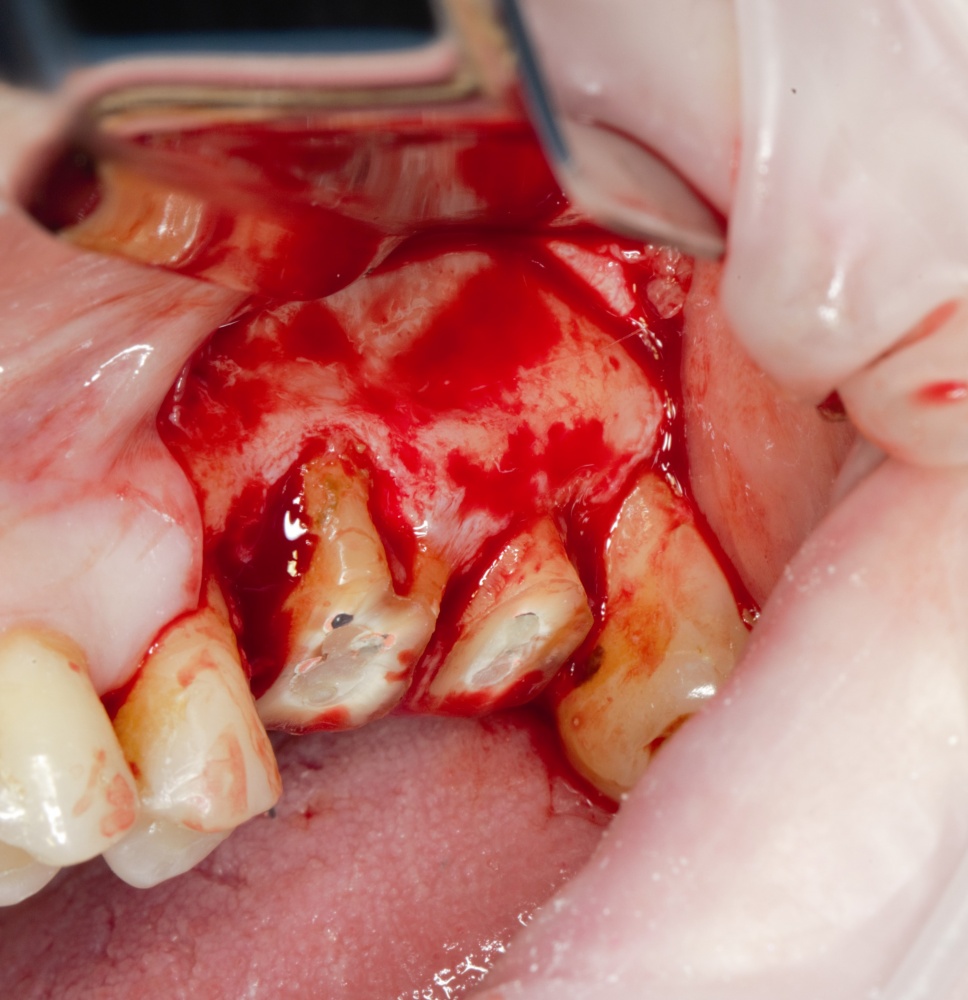

Кстати, обрати внимание на ширину альвеолярного гребня (левая картинка). Она чуть меньше 3 мм. Это объясняет, почему я засомневался в возможности установки имплантатов одновременно с остеопластикой. Понятно и без КЛКТ.

Возвращаемся к основной операционной области. Еще раз посмотрим на альвеолярный гребень, поофигеваем от его ширины и моих грандиозных планов: